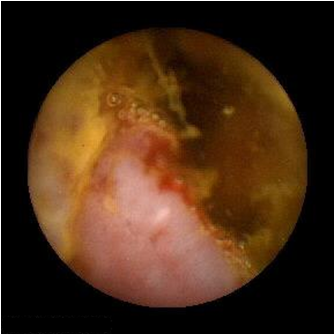

④胶囊内镜

胶囊内镜检查过程

胶囊内镜检查只需三个简单的步骤 , 即可完成检查:吞服胶囊,拍摄记录,回放观察。

胶囊内镜通过采集、储存、回放全小肠粘膜彩色图像,能够直接观察全小肠粘膜,敏感性高,是目前唯—的无 创、可视的全小肠检查手段。适用于各个年龄层次的患者,尤其是合并心、肺、脑、肾等 多 脏器疾病的患者,以及难以耐受内镜及其他有创检查的老年患者。

间质瘤

克罗恩病变

息肉样病变

血管瘤

原发性腺癌

脂肪瘤

胶囊内镜主要适用于不明原因的腹痛、腹泻、消化道出血、小肠肿瘤、克罗恩氏病等小肠疾病的诊断。本检查适用于:

1、不明原因消化道出血2、不明原因缺铁性贫血3、小肠肿瘤(良性、恶性及类癌等)4、无法解释的腹痛、腹泻5、各种炎性肠病6、其他检查提示的小肠影像学异常